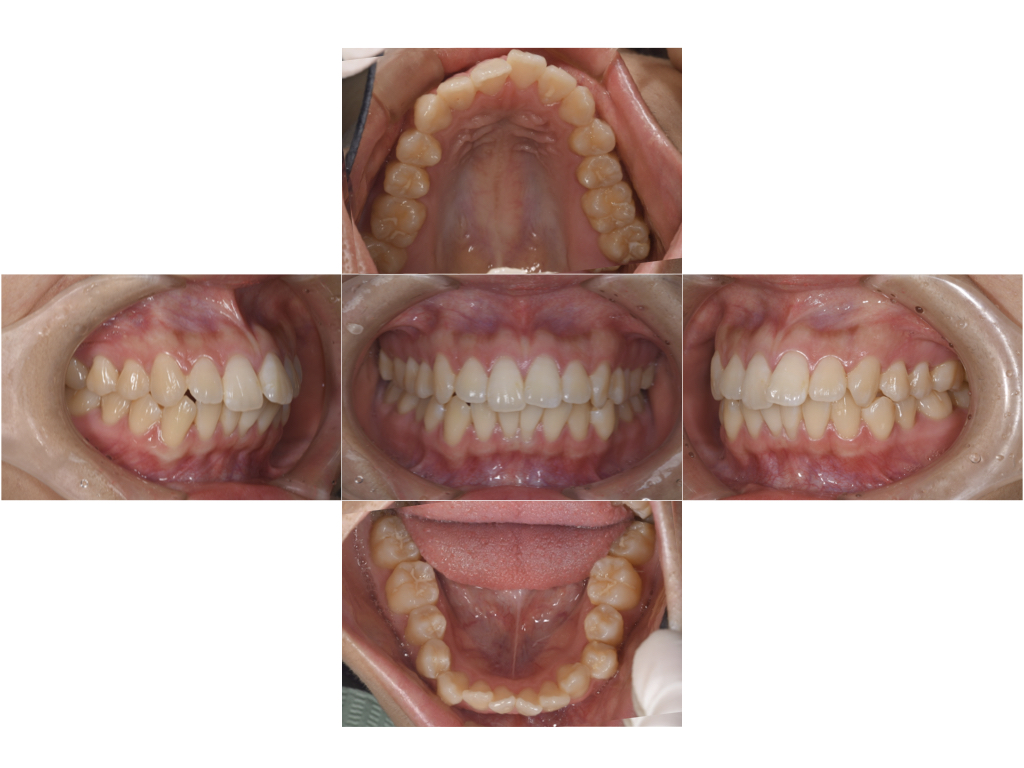

口腔内スキャナーのiTeroを用いてシミュレーションを行い、矯正後のイメージを実際に見ていただいた上で、インビザラインにて矯正治療を行なった。

実質動的期間は14週でシミュレーション通りに終了し、仕上がりにも大変満足していただいた。